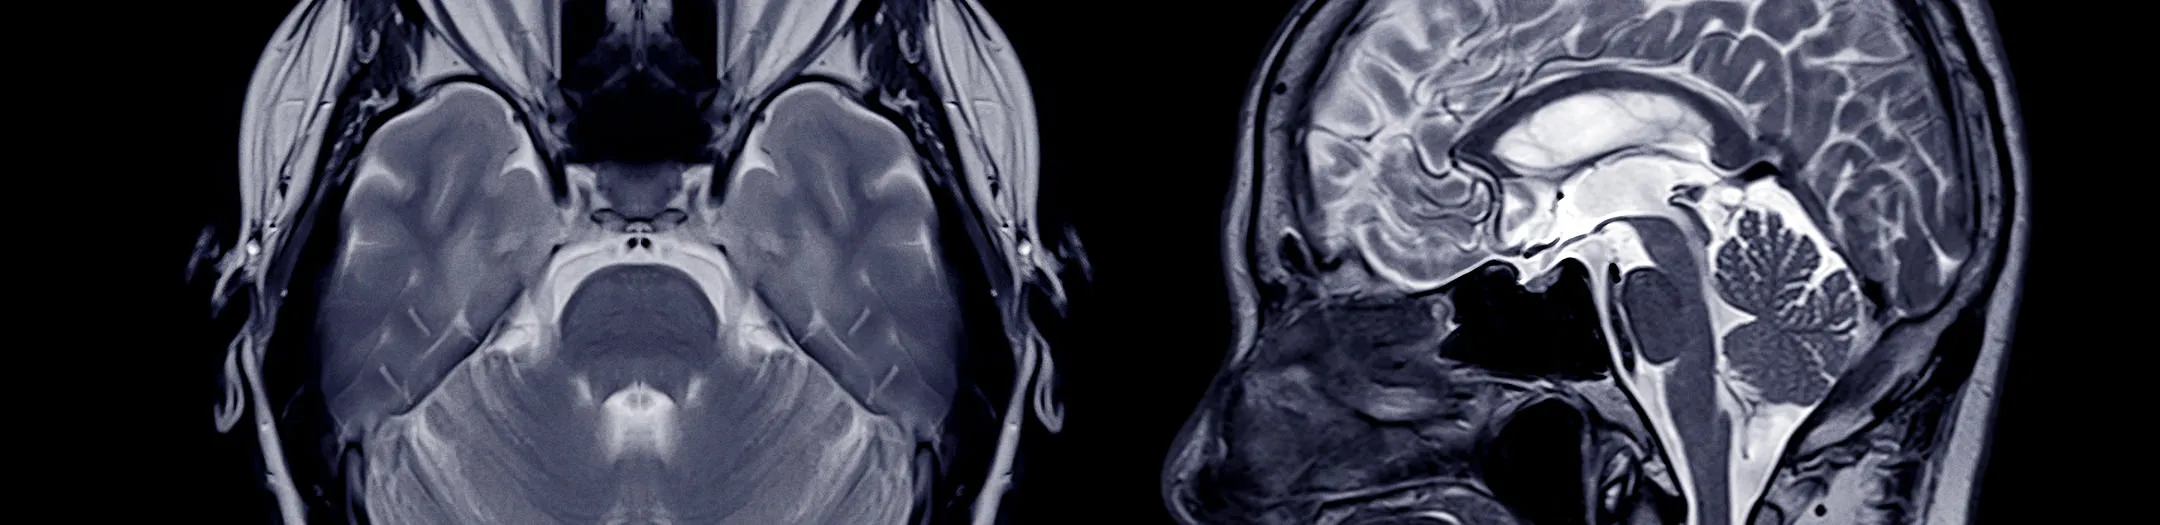

For radiology clinics: New revenue streams with minimal administrative overhead